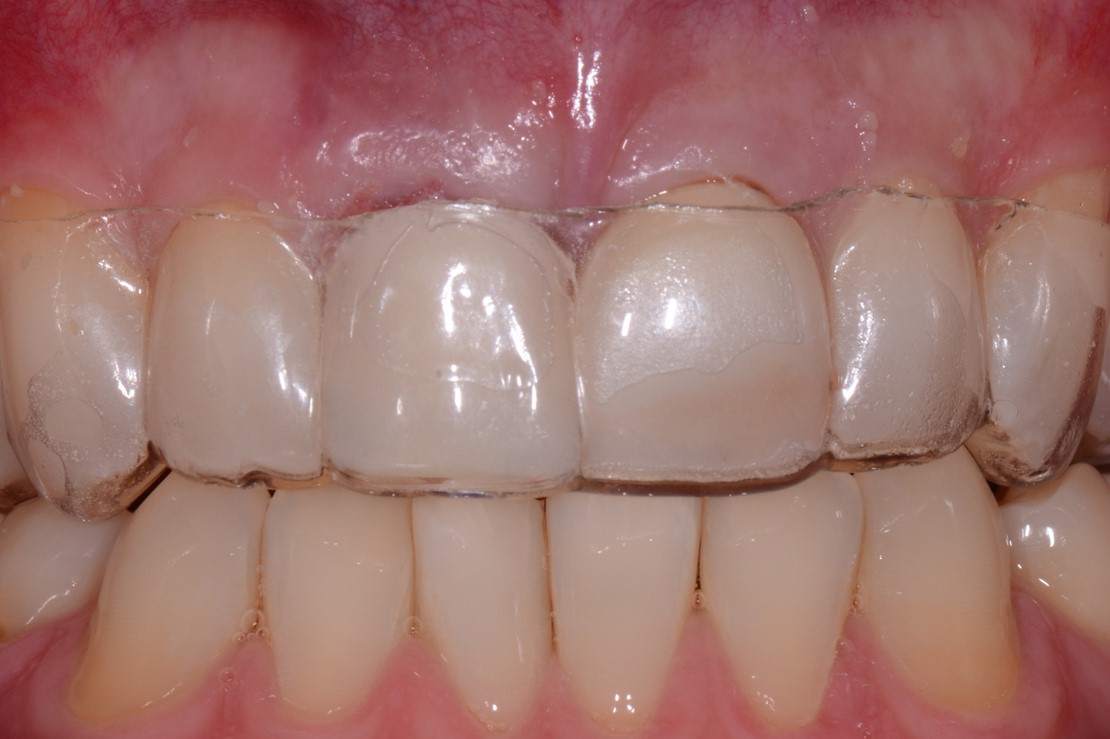

Fig 24. View of the uncovered implant and now-prepared adjacent tooth for finalizing prosthetic treatment

Figure 24

Fig 25. Post-treatment, healthy bone and ideal implant placement were observed radiographically.

Figure 25

Fig 26. The results of this esthetic treatment is an inconspicuous implant-supported crown restoration.

Figure 26

Second-stage surgery involved uncovering the implant and finalizing the prosthetic treatment (Figure 24). The ultimate outcome represented a thickened biotype, healthy bone (Figure 25), and an inconspicuous implant-supported crown restoration (Figure 26).